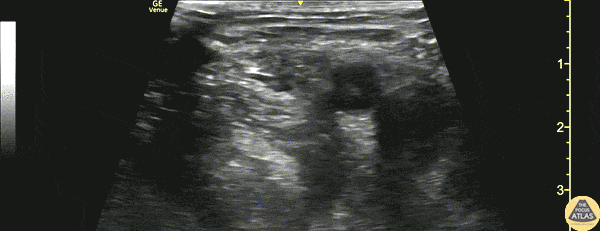

A 60s F presented to the ED with hip/leg pain after a mechanical slip and fall. She had an obvious closed deformity of the proximal femur on exam, and radiographs demonstrated an intertrochanteric femur fracture with subtrochanteric extension. After consultation with orthopedic surgery, a fascia iliaca block was performed to provide analgesia and to facilitate traction radiographs, and she was admitted for surgery. This clip shows the block being performed, with the needle entering from left of screen (laterally), depositing anesthetic just deep to the fascia iliaca, superficial to the iliacus muscle. The femoral artery and vein can be seen to the right (medial) of the area of injection. Dr. Arian Anderson, PGY4, and Dr. Michael Heffler, PGY3 Denver Health Residency in Emergency Medicine